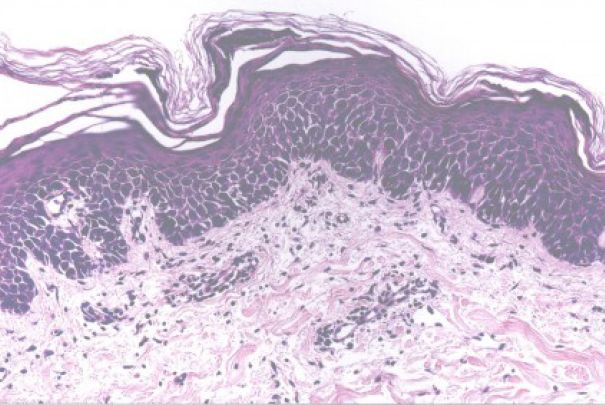

紅皮病又稱剝脫性皮炎,是一種嚴(yán)重的全身性疾病,一般認(rèn)為紅皮病與剝脫性皮炎為同一種疾病,前者以廣泛的紅斑浸潤伴有糠秕狀脫屑為特征,而后者存在廣泛性水腫性紅斑,伴有大量脫屑。皮膚受累面積≥90%是診斷本病的先決條件。